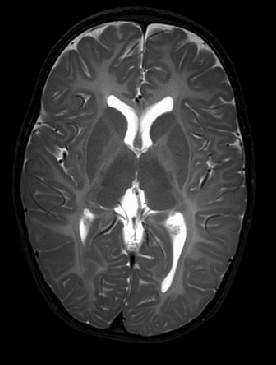

“White Brain”

ROI #1: Basal Ganglia

Single Voxel MRS Spectrum automatically generated, saved to PACS.

MRS ROI #2: Watershed White Matter

Multivoxel : Remember to manually screen save your ROI image.